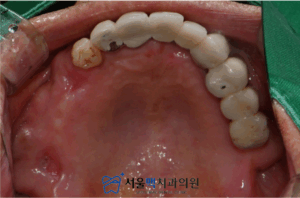

처음 내원하셨을 때의 모습입니다.

오른쪽 위(사진에서 왼쪽) 작은어금니를 포함한

여러 치아가 상실된 것을 볼 수 있는데요.

가양역임플란트, 서울맥치과는

환자분의 정확한 치조골과

상악동의 상태를 확인하기 위해

3D CT 촬영을 진행하였습니다.